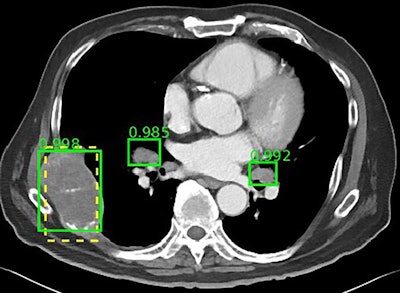

The NIH DeepLesion database includes more than 32,000 CT slices. Image courtesy of the NIH.With a multicategory lesion database, DeepLesion offers researchers the opportunity to develop AI algorithms capable of automating radiological detection and diagnosis for multiple lesion types, the NIH noted. It can also open the possibility of a universal lesion detector that would serve as an initial screening tool and would send its results to other, more specialized algorithms. Furthermore, researchers may be able to study the relationship between distinct kinds of lesions on the same CT scan for whole-body assessment of cancer burden.

To begin demonstrating this potential, Summers and colleagues used the DeepLesion database to train a prototypical universal lesion detector to spot various kinds of lesions. Their detector achieved a sensitivity of 81.1%, with five false positives per image (Journal of Medical Imaging, July 20, 2018).